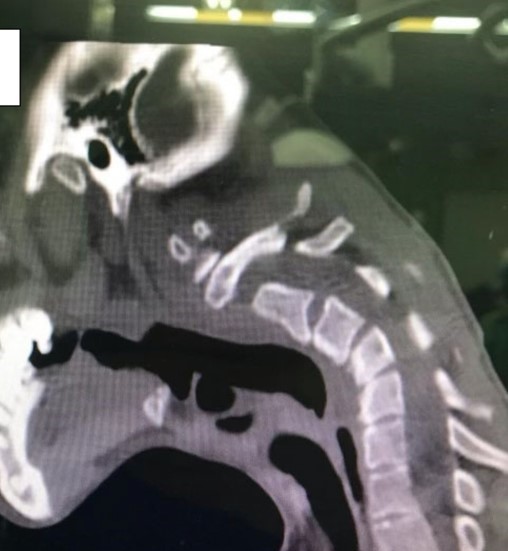

根據媒體《Dailymail》的報導,伊朗伊斯法罕扎赫拉大學醫院在公布了幾張病例照,揭示吸毒鮮為人知的嚴重後果。一名23歲的男子因為長年濫用藥物,結果導致頸部90度彎曲,無法再支撐頭部,被確診「頭部下垂症候群 (Dropped head syndrome)」。除此之外,男子還經歷了慢性頸部疼痛和感覺異常,手臂有刺痛、麻木或針刺感。

圖片來源 / 翻攝自Clinical Case Reports

據了解,「頭部下垂症候群」主要病徵是頸椎兩旁的肌群出現嚴重無力現象,導致頭部及頸椎慢慢地下垂前傾,濫用藥物就是可能病因之一。不過藥物本身不會直接對肌肉骨骼造成變化,而是間接影響,醫生就指出,男子就是在使用毒品時,長時間維持頸後凸的姿勢,這才讓頸椎嚴重變形,男子情況也確實罕見。